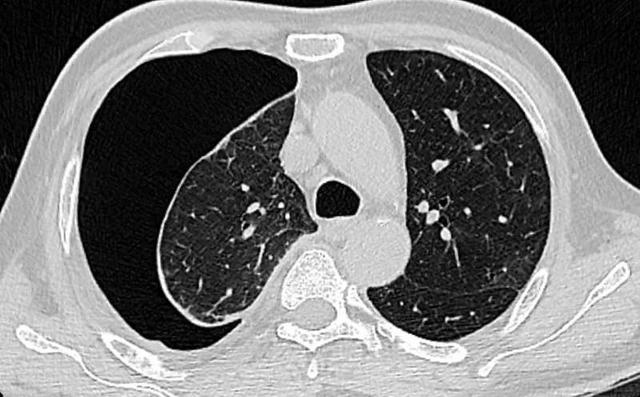

醫(yī)生檢查后發(fā)現(xiàn),小玲的右肺像氣球一樣被扎破了,胸腔內(nèi)充氣形成右側(cè)氣胸,右肺已被壓縮40%,必須立即進(jìn)行手術(shù)將漏氣“放出”。